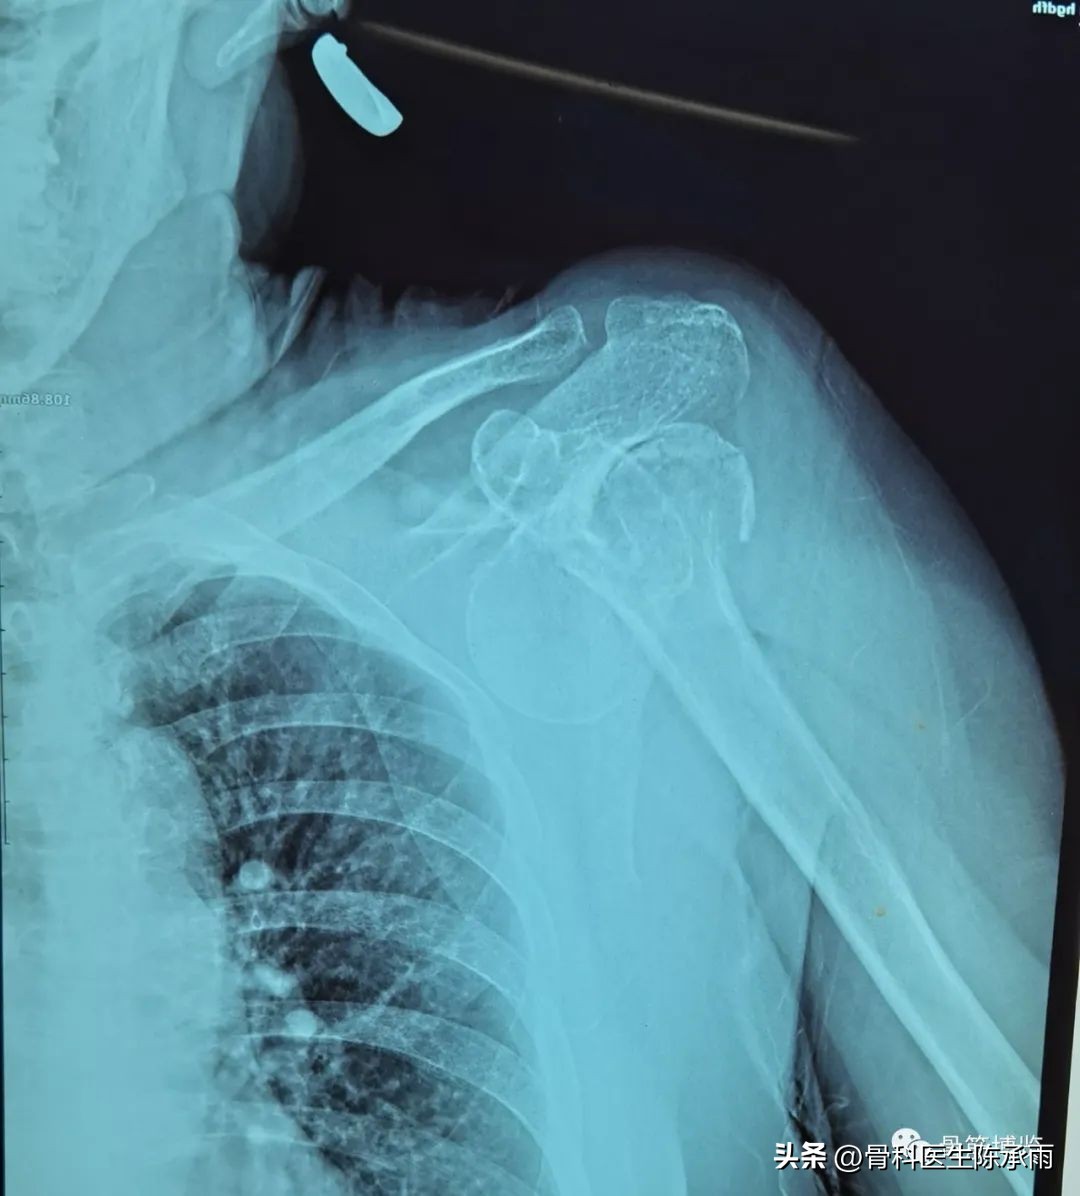

肱骨外科颈骨折是指肱骨解剖颈下2~3 cm处的骨折,亦称膈骨肩端骨折。肱骨外科颈位于肱骨大小结节下缘与肱骨干的交界处,该处骨松质较多,骨皮质薄,无肌肉附着,是肱骨干和肱骨上端的衔接部,在直接*力暴**或间接*力暴**作用下,易致骨折,是全身骨折的好发部位之一。有研究证明引起该部骨折的主要诱发原因是骨质疏松。研究还发现在肱骨上端有赖以维持肱骨完整性和坚韧性的两个骨小梁系统。一条是通过肱骨头下部的中束,另一条通过肱骨大结节垂直下行和通过肱骨头外上的骨小梁系统。这两条骨小梁系统都与肱骨的静止负载能力有关,通过肱骨外科颈部的这两条骨小梁系统的削弱是引起骨折的常见原因。紧靠肱骨外科颈内侧有腋神经向后进入三角肌内,臂丛神经、腋动静脉经过腋窝,骨折端严重移位时可合并神经血管的损伤。

术中见肱骨头脱位 ,肱二肌长头腱嵌于关节盂处较难复位,关节囊大部分撕裂,冈上下肌止点处撕脱骨折,肩胛下肌止点处撕脱骨折,术中复位固定,重建三肌止点。并缝合前侧关节囊。